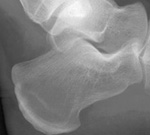

What abnormality is shown here?